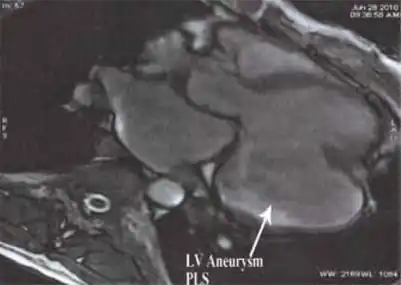

Heart left ventricular aneurysm short axis view

Ventricular aneurysms are one of the many complications that may occur after a heart attack. The word aneurysm refers to a bulge or 'pocketing' of the wall or lining of a vessel commonly occurring in the blood vessels at the base of the septum, or within the aorta. In the heart, they usually arise from a patch of weakened tissue in a ventricular wall, which swells into a bubble filled with blood.[1] This, in turn, may block the passageways leading out of the heart, leading to severely constricted blood flow to the body. Ventricular aneurysms can be fatal. They are usually non-rupturing because they are lined by scar tissue.